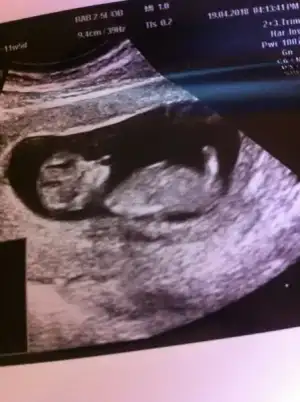

Günaydın anneler dün 2li tarama testi için hastanedeydik 11+5 di Adet tarihime göre ama doktor 12+3 ölçtü 5 gün ilerde gidiyor bebeğinin gelişimi çok güzel dedi çok şükür ense kalınlığı da ölçüldü ölçümlernde hiçbir problem görülmedi rabbime şükür ama cinsiyet konusunda 2 tane doktora girdik biri ultrasoncu biri kendi doktorum ikiside çok ketun çıktı bir tahminde bulunmak istemediler :( bende sizlerden rica ediyorum yorumlarmısınızz. İlgilenen herkese teşekkür ederim

Eklentiler

• image.webp

image.webp

19,5 KB · Görüntüleme: 110

• image (1).webp

image (1).webp

17,2 KB · Görüntüleme: 103